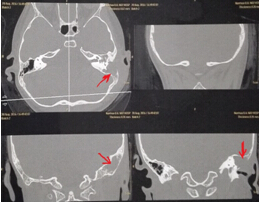

該患兒既往無中耳炎及耳流膿病史,僅表現(xiàn)為1個(gè)月前耳后稍有紅腫、疼痛,在當(dāng)?shù)蒯t(yī)院曾被診斷為“蚊蟲咬傷”所致,家長也未引起足夠的重視。近半月來,患兒耳后紅腫疼痛加重,遂到我市某三甲醫(yī)院就診,行高分辨率中耳乳突CT,發(fā)現(xiàn)側(cè)顱底、中耳乳突腔巨大新生物占位,乳突骨皮質(zhì)破壞吸收,并可疑耳后骨膜下膿腫形成。病情若進(jìn)一步發(fā)展,膽脂瘤破壞顱底骨質(zhì),將極有可能并發(fā)腦膜炎、腦膿腫,甚至出現(xiàn)敗血癥、腦疝等,危及生命。

3.術(shù)前CT2 4.術(shù)中術(shù)腔中的巨大膽脂瘤